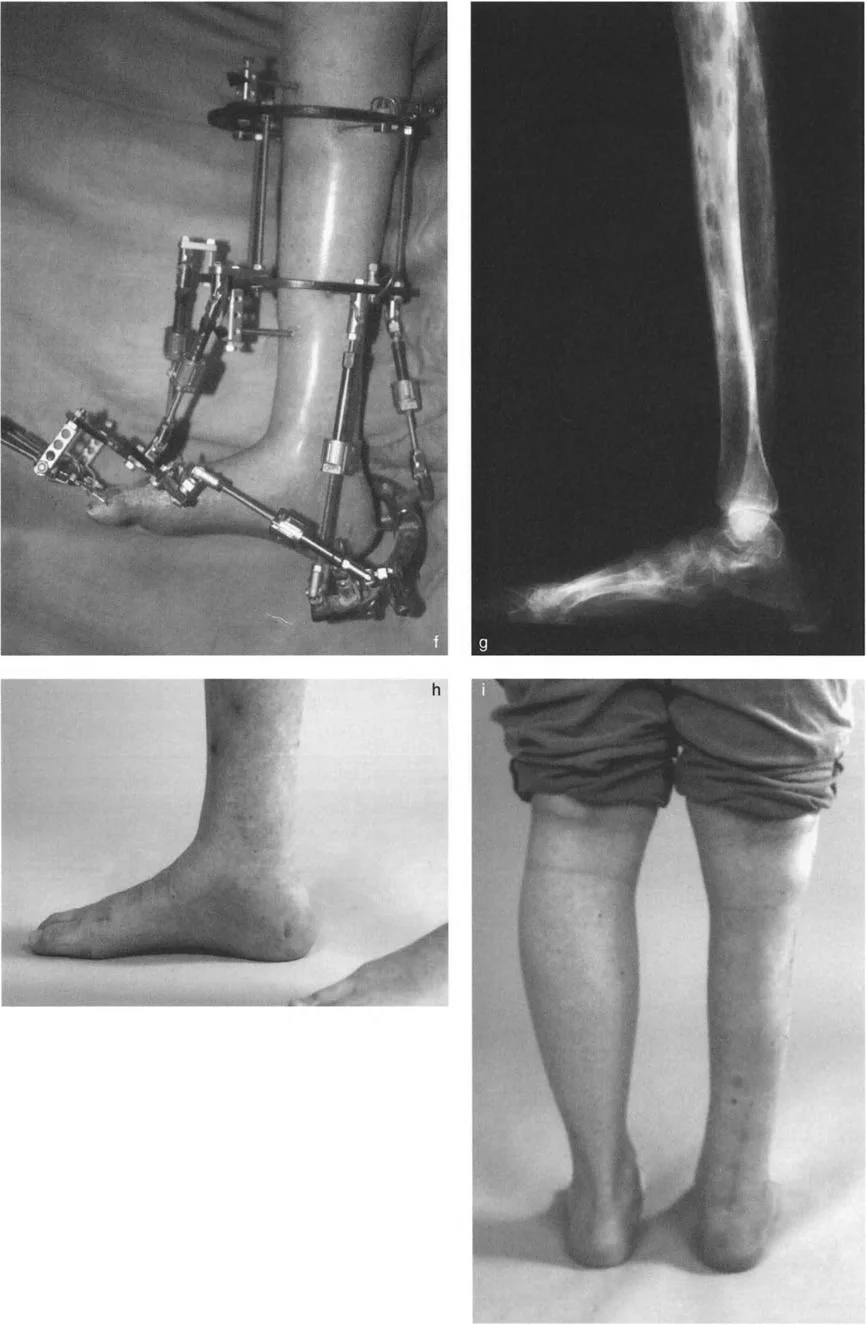

- صورة توضح تقلصًا في الكاحل بزاوية 20 درجة.

- صورة شعاعية توضح تقلصًا في الكاحل بزاوية 20 درجة.

خيارات علاج تقوس وتشوهات الكاحل والقدم

يعتمد علاج تشوهات الكاحل والقدم على السبب الكامن وراء التشوه وشدته، بالإضافة إلى عمر المريض وحالته الصحية العامة. يقدم الأستاذ الدكتور محمد هطيف مجموعة واسعة من الخيارات العلاجية، بدءًا من التدخلات التحفظية وصولًا إلى الجراحات المتقدمة باستخدام أحدث التقنيات.

التدخلات الجراحية المتقدمة

يتمتع الأستاذ الدكتور محمد هطيف بخبرة واسعة في إجراء مجموعة متنوعة من العمليات الجراحية لتصحيح تشوهات الكاحل والقدم، بما في ذلك:

إزالة النتوءات العظمية وتعميق التلم الكاحلي

في حالات تقوس الكاحل الناتجة عن اصطدام عظمي (Bony Impingement) بسبب نتوءات عظمية في حافة الظنبوب الأمامية أو في التلم الظهري لعظم الكاحل، يقوم الأستاذ الدكتور محمد هطيف بإزالة هذه النتوءات وتعميق التلم الكاحلي للسماح لعظم الكاحل بالثني للأعلى بحرية.

قطع العظم التصحيحي (Osteotomy)

عند وجود تشوهات عظمية مثل تقوس الظنبوب البعيد، قد يتطلب الأمر قطع العظم وإعادة توجيهه. على سبيل المثال، يمكن إجراء قطع عظم قبة ظهرية (Dorsiflexion focal dome osteotomy) في الظنبوب البعيد لتصحيح انحنائه.